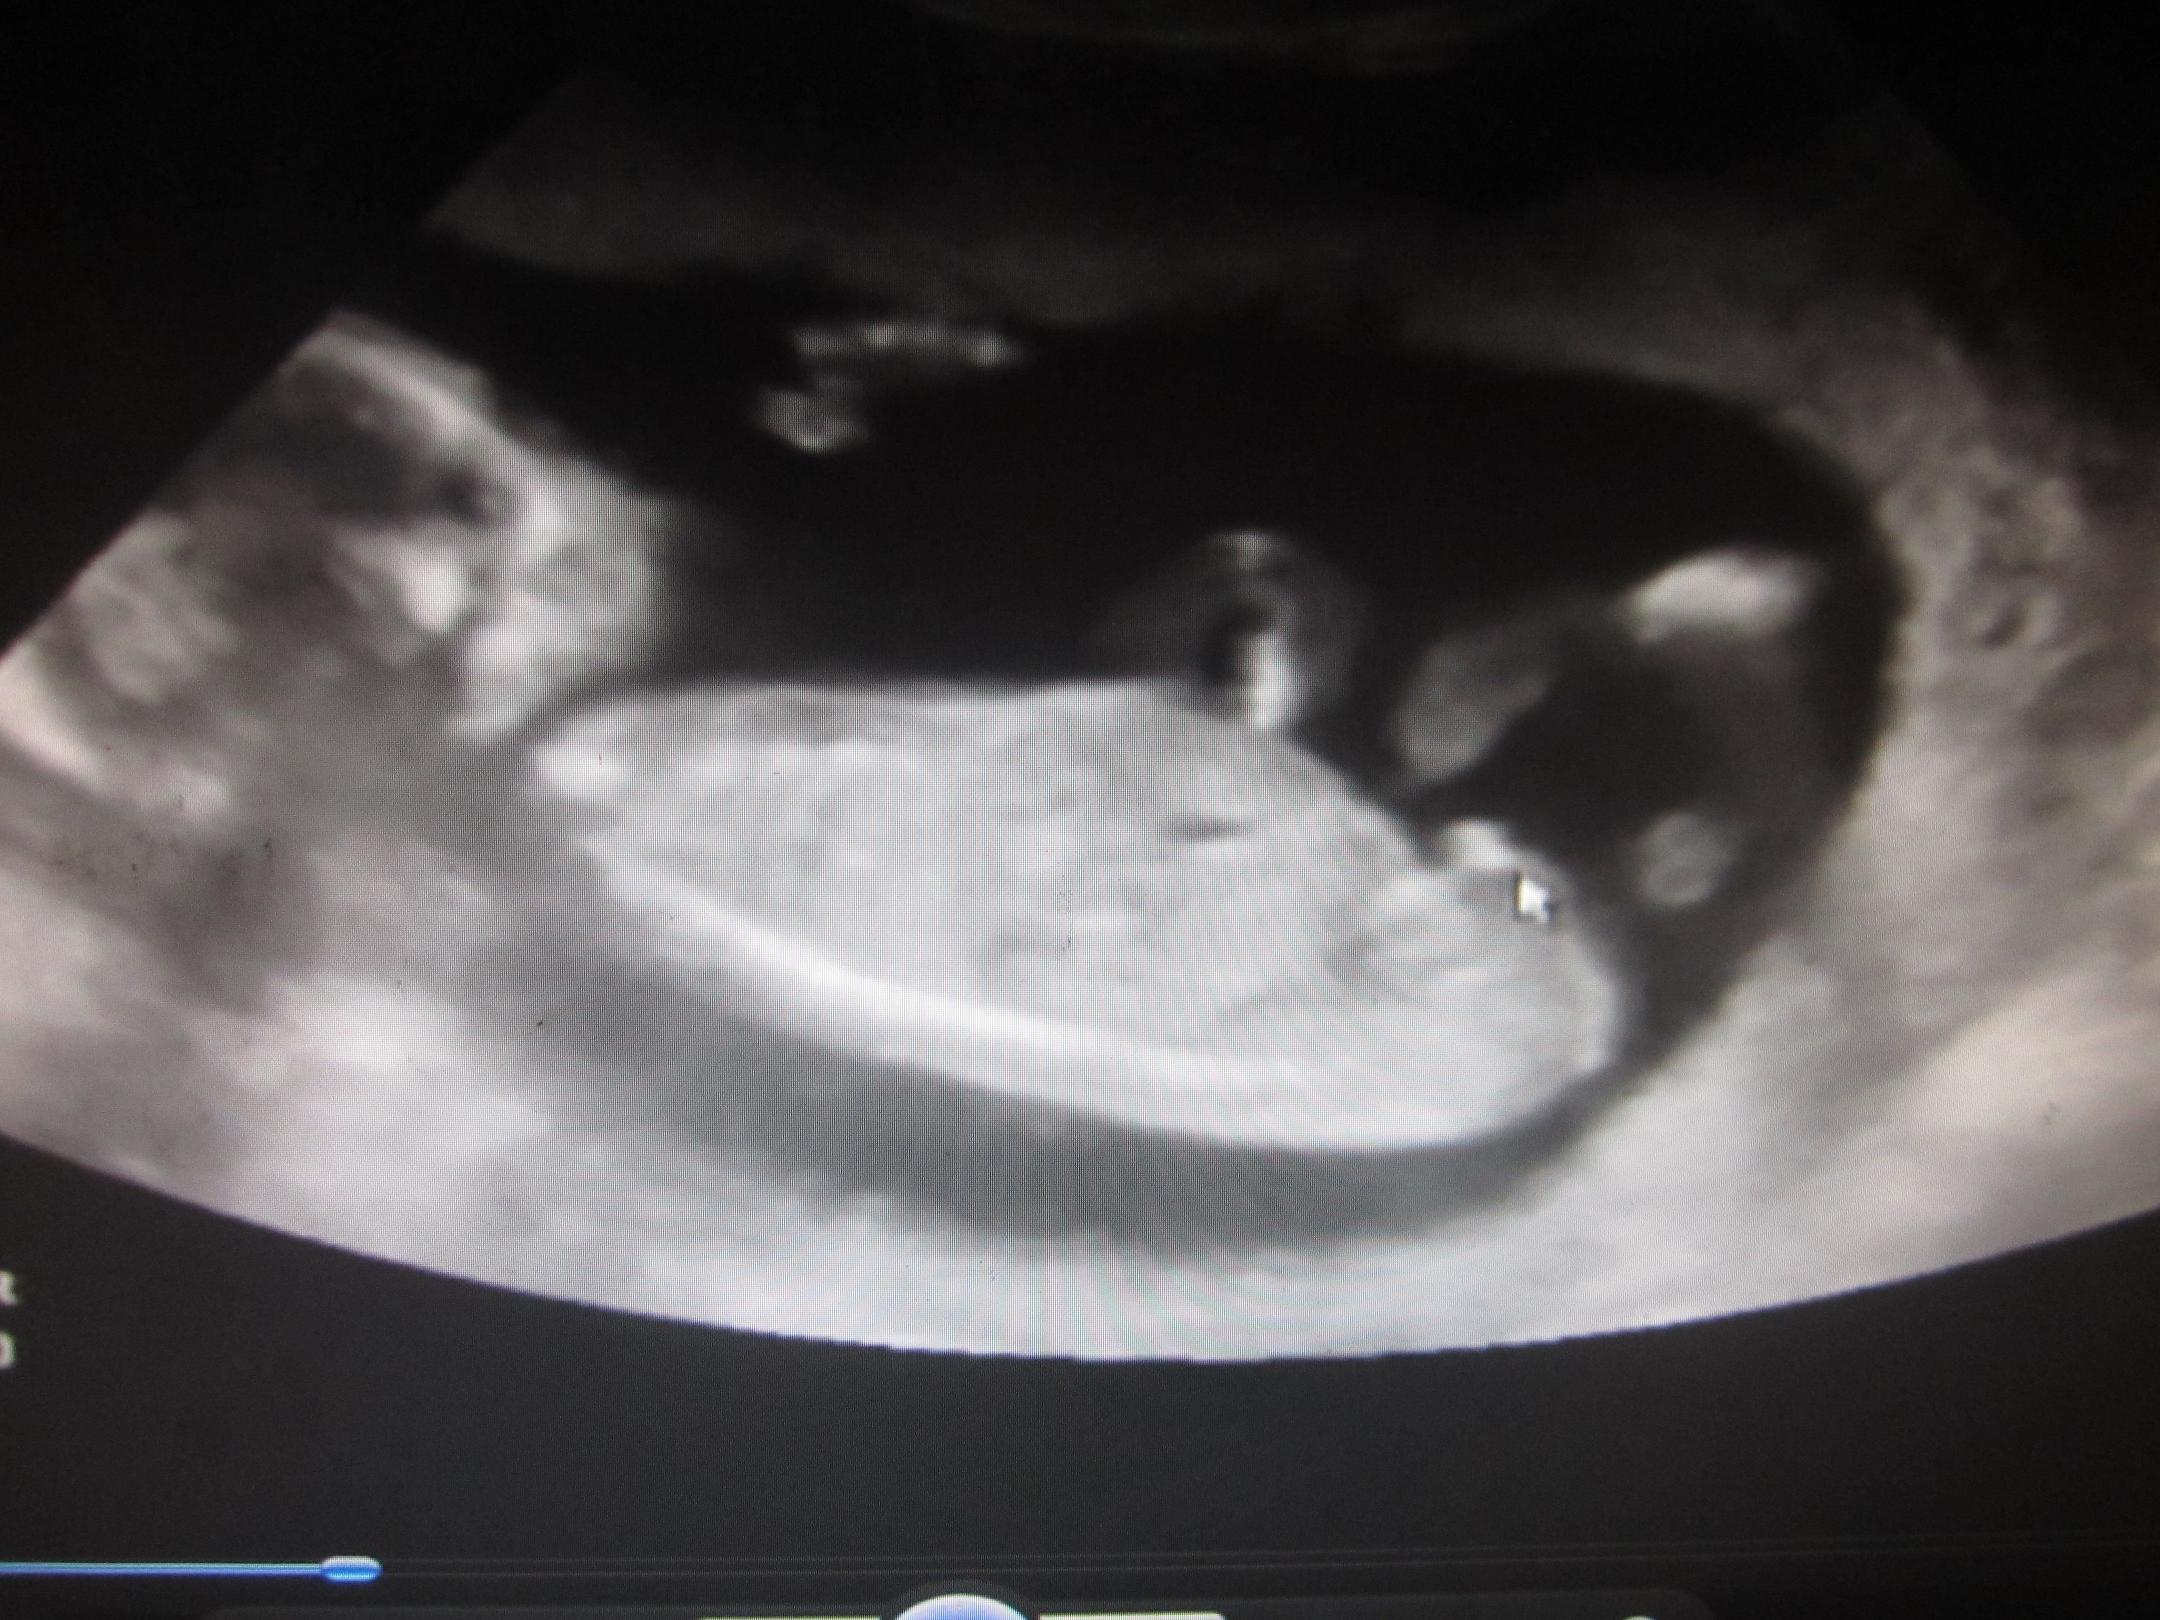

I had a scan today im 17 weeks and the tech said its definatly a BOY :)

Attachment 6899

This is the profile and the arrow is pointing to the scrotum and willy. Tech said see how it is pointing in that direction, thats classic boy.